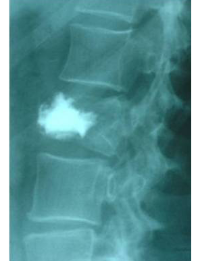

Comparació pre- i post-operatoria d’una cifopastia cementada

Dona, edat 55 anys, fractura aixafament dret de L2

Abans 2

Després 2